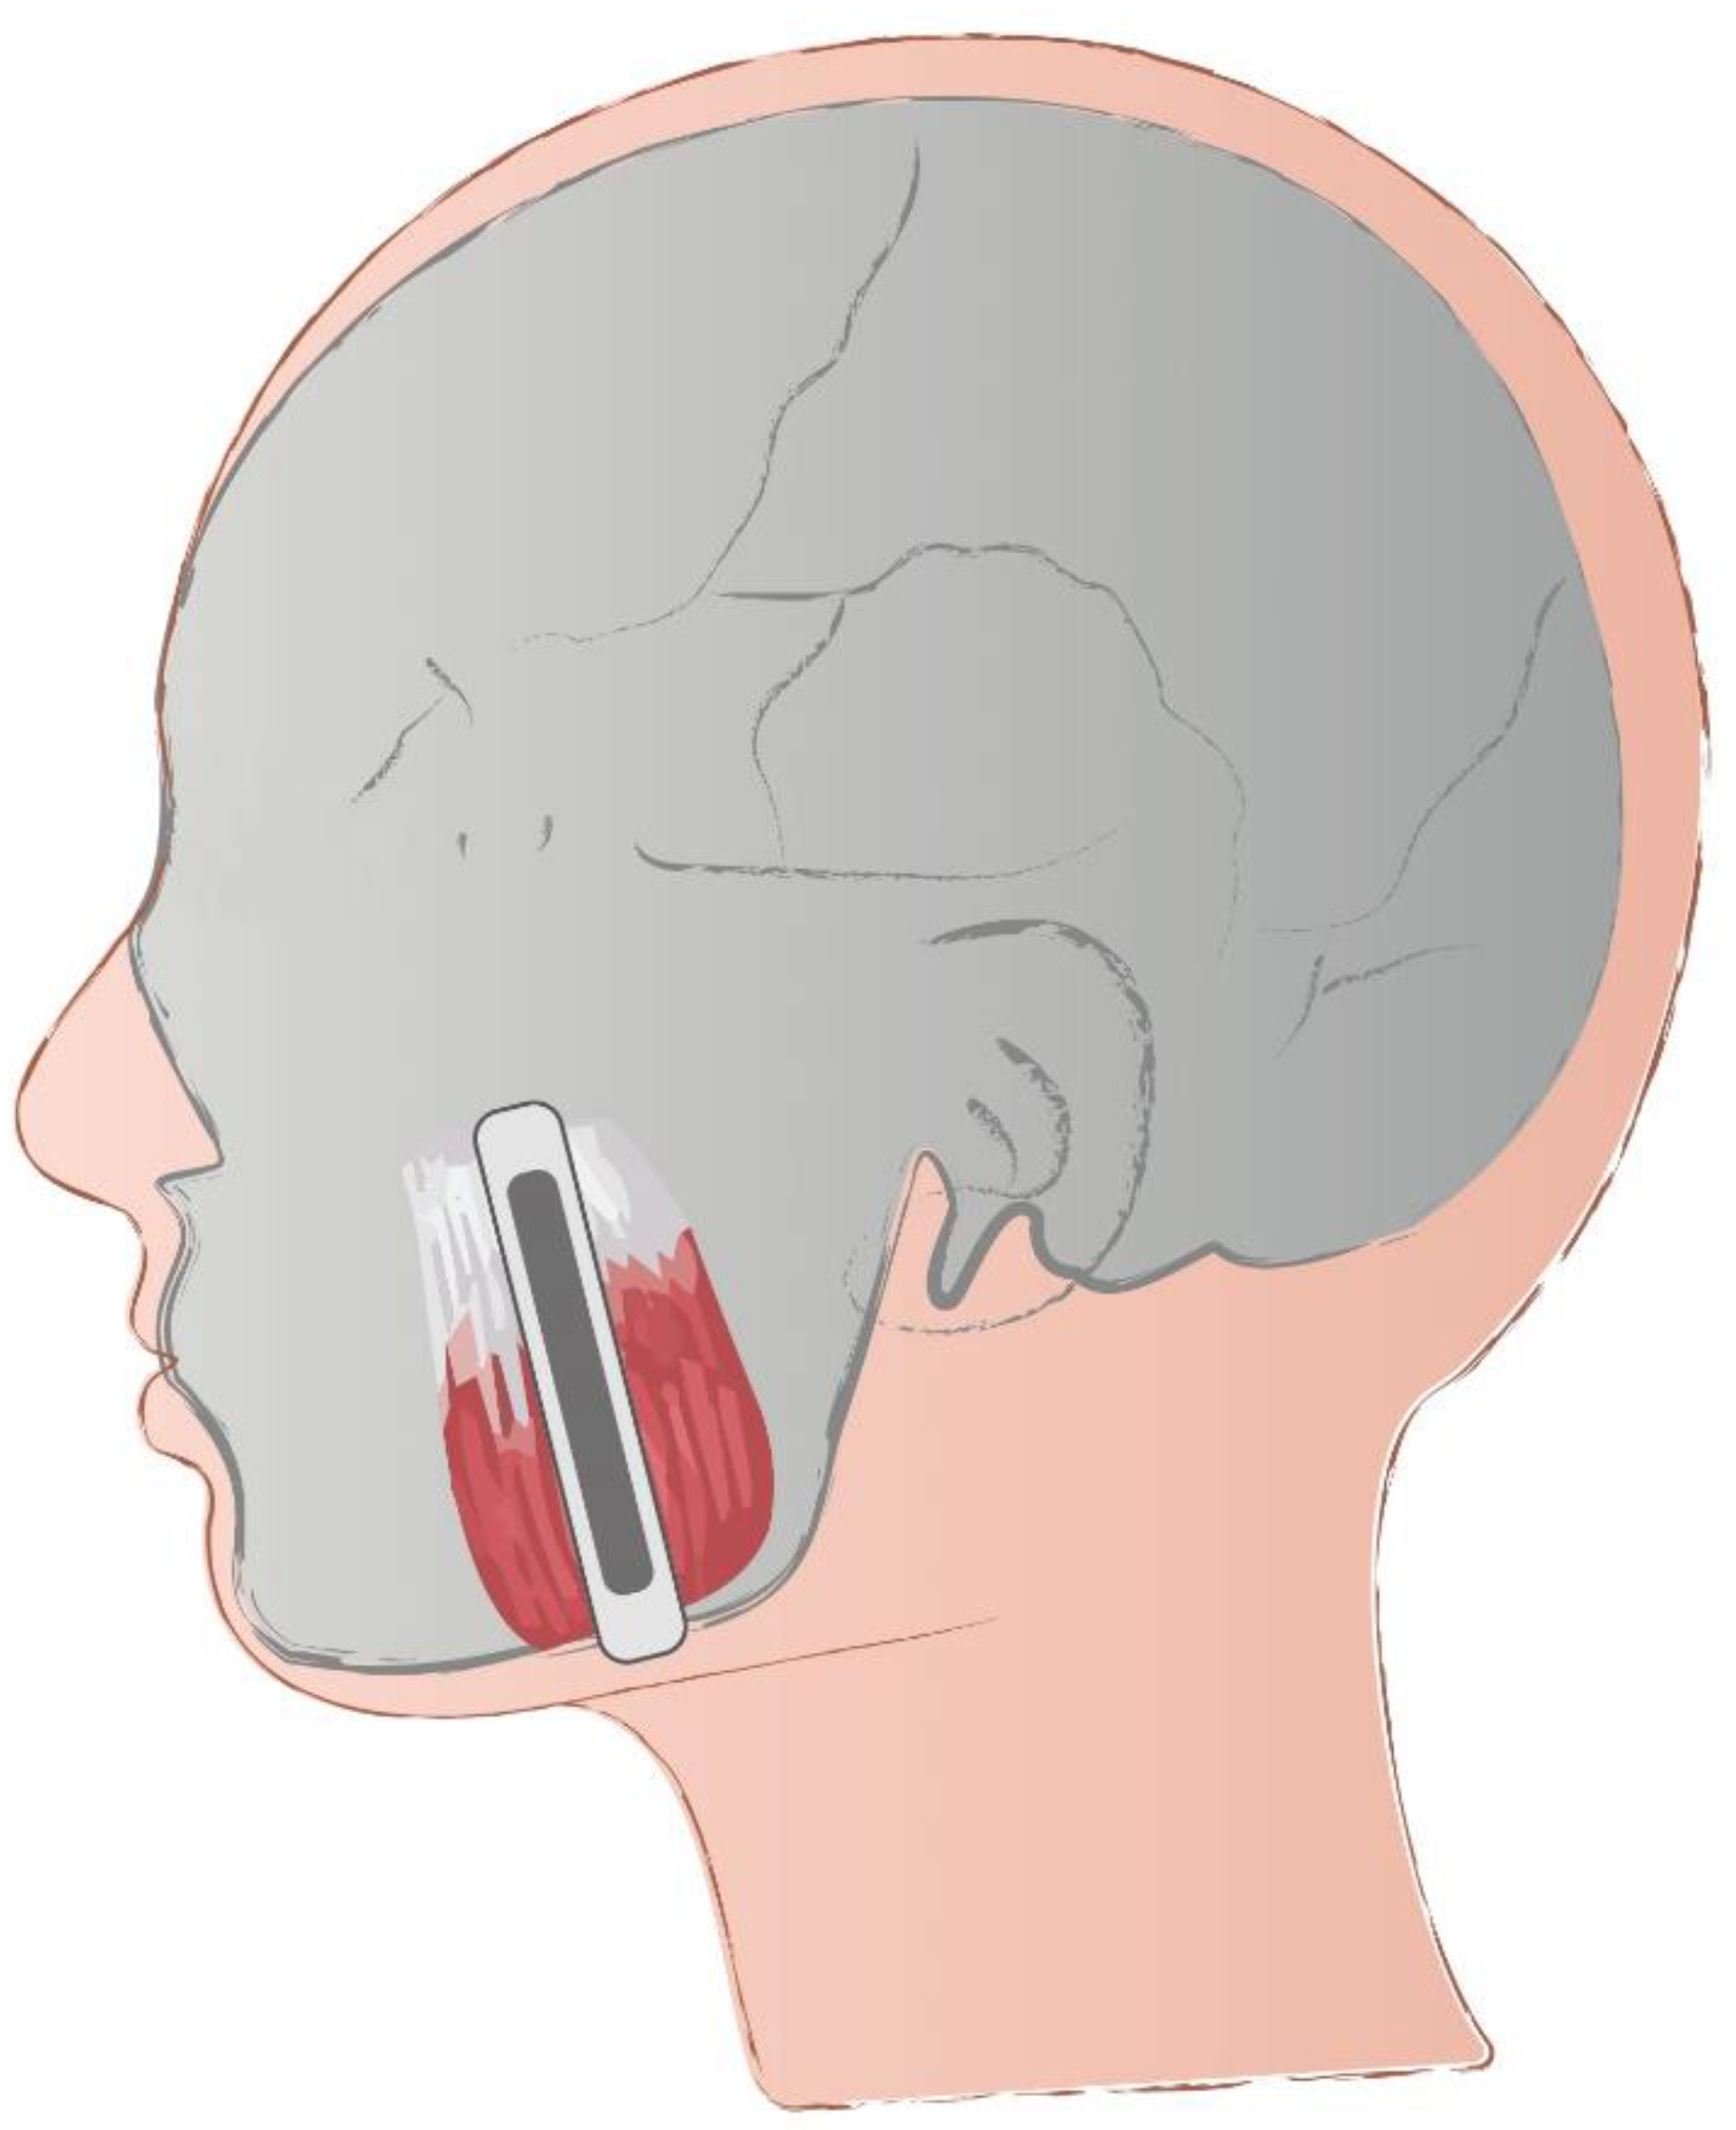

2. Materials and Methods